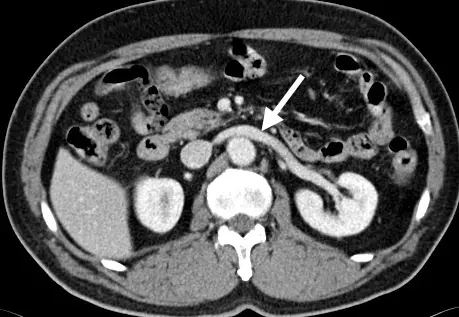

下圖中箭號所示的解剖構造為何?

- 影像基礎:此為腹部對比劑增強電腦斷層(Contrast-enhanced CT)的軸狀(Axial)影像。從血管高亮顯影的程度(特別是下腔靜脈與腎臟皮髓質的顯影狀況)可以看出處於靜脈期(Venous phase)。

- 解剖標記(Landmarks):

- 影像下方中央為脊椎。

- 脊椎前方、偏影像右側(人體左側)的正圓形高亮血管為腹主動脈(Abdominal aorta)。

- 腹主動脈右側(影像左側,人體右側)較扁平的巨大血管為下腔靜脈(Inferior vena cava, IVC)。

- 影像左右兩側的實質化器官為雙側腎臟。

- 箭號所指構造:白色箭號指著一條管狀的血管構造,我們可以看到它起源自左側腎臟(影像右側)的腎門,向人體右側橫跨中線。

- 關鍵空間關係:這條血管在橫越中線時,行經腹主動脈的「前方」,同時又穿過另一條較小